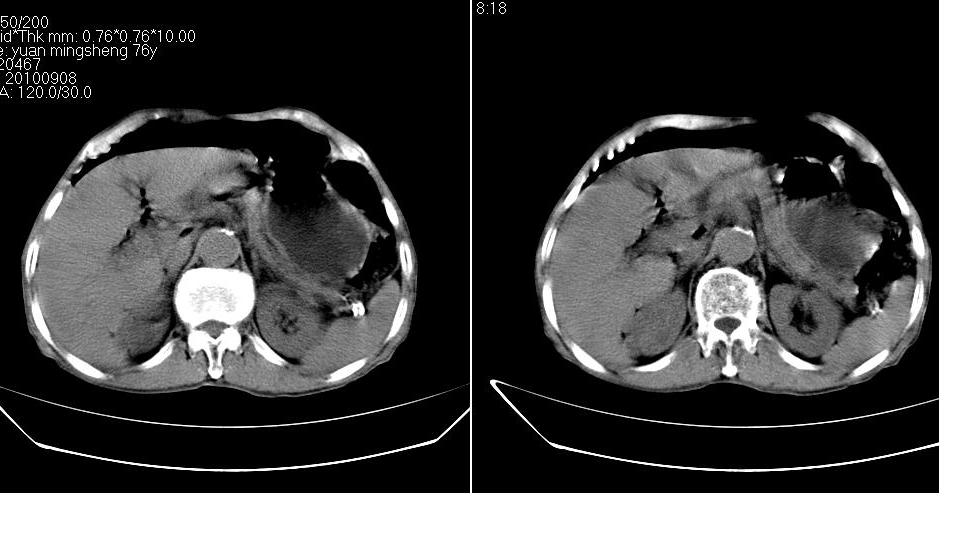

男,76岁,上腹部疼二天来就诊,彩超提示肝左叶占位,随后做上腹部ct平扫,今天做上腹部ct增强扫描,手工推药,效果不好,请谅解。

肝左叶s4肿块强化形式大概是:慢进慢出,逐渐强化----考虑血管瘤/腺瘤?{动脉期应更提前扫}。

肝右叶前段hcc

1)肝右叶前段低密度灶,不排除肝癌可能;建议查afp。2)右肾上极囊肿。

肝内胆管积气扩张,胆囊增大,肝右前叶低密度灶,逐渐强化,一元论,胆系感染,局限性肝脓肿;右肾囊肿。

考虑肝s4段肝脓肿可能?未排除肝癌。右肾上极囊肿。